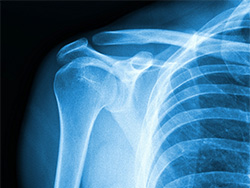

四十肩

四十肩とは